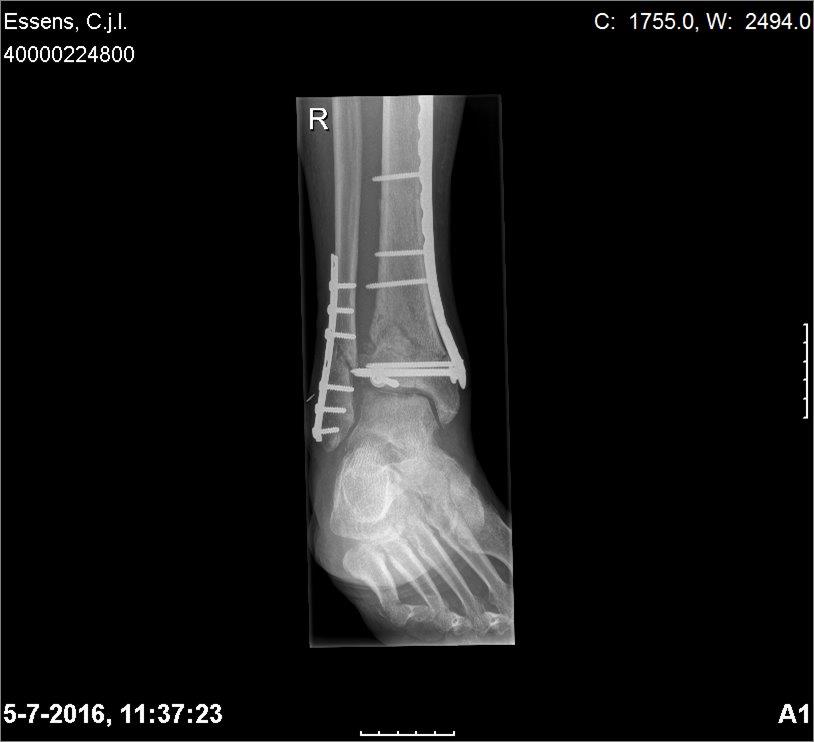

Goed te horen dat er iig genoeg herstel is om het osteoporose materiaal te verwijderen.

Wel balen van de beperking met trainen maar je kan iig nu weer vooruitkijken met opbouwen.

Maar de arts ziet kennelijk wel verschil neem ik aan?Eerlijk gezegd zie ik niet veel verschil lees vooruitgang met de foto's van 28 maart jongstleden

Operatie zal september zijn vermoed ik